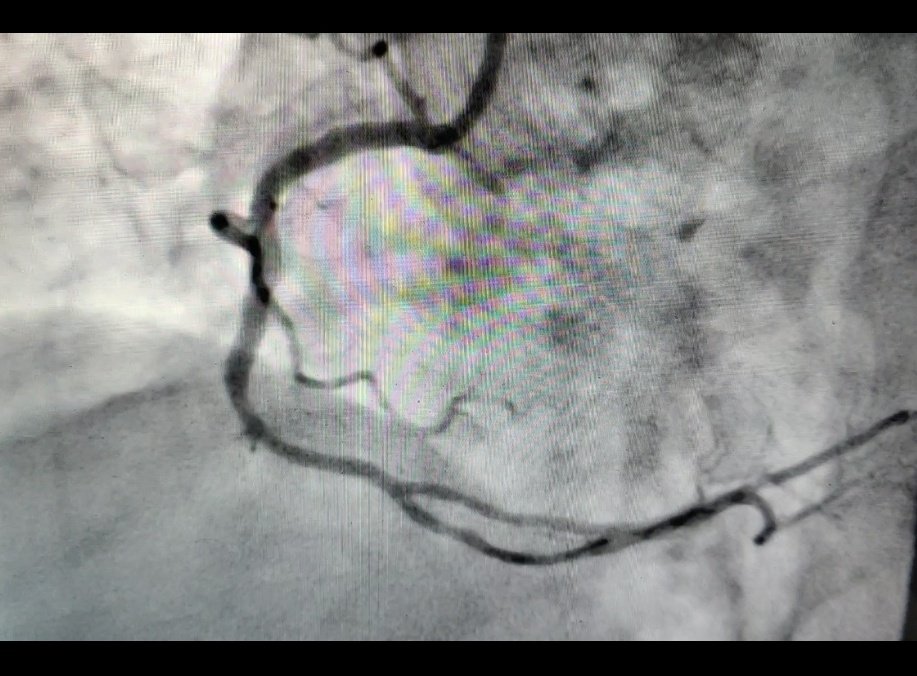

4. Final result (further pd with 2.75nc baloon distally) #rotatripsy. Important to image post rotablation before stent, as may not have appreciated napkin Ca persistence after rotablation. @AntoniousAttall @hect2701 @jmahmed @mirvatalasnag @MarcoJe80135689 @naderjo @SukhNijjer

mmamas1973's tweet image. 4. Final result (further pd with 2.75nc baloon distally) #rotatripsy. Important to image post rotablation before stent, as may not have appreciated napkin Ca persistence after rotablation. @AntoniousAttall @hect2701 @jmahmed @mirvatalasnag @MarcoJe80135689 @naderjo @SukhNijjer